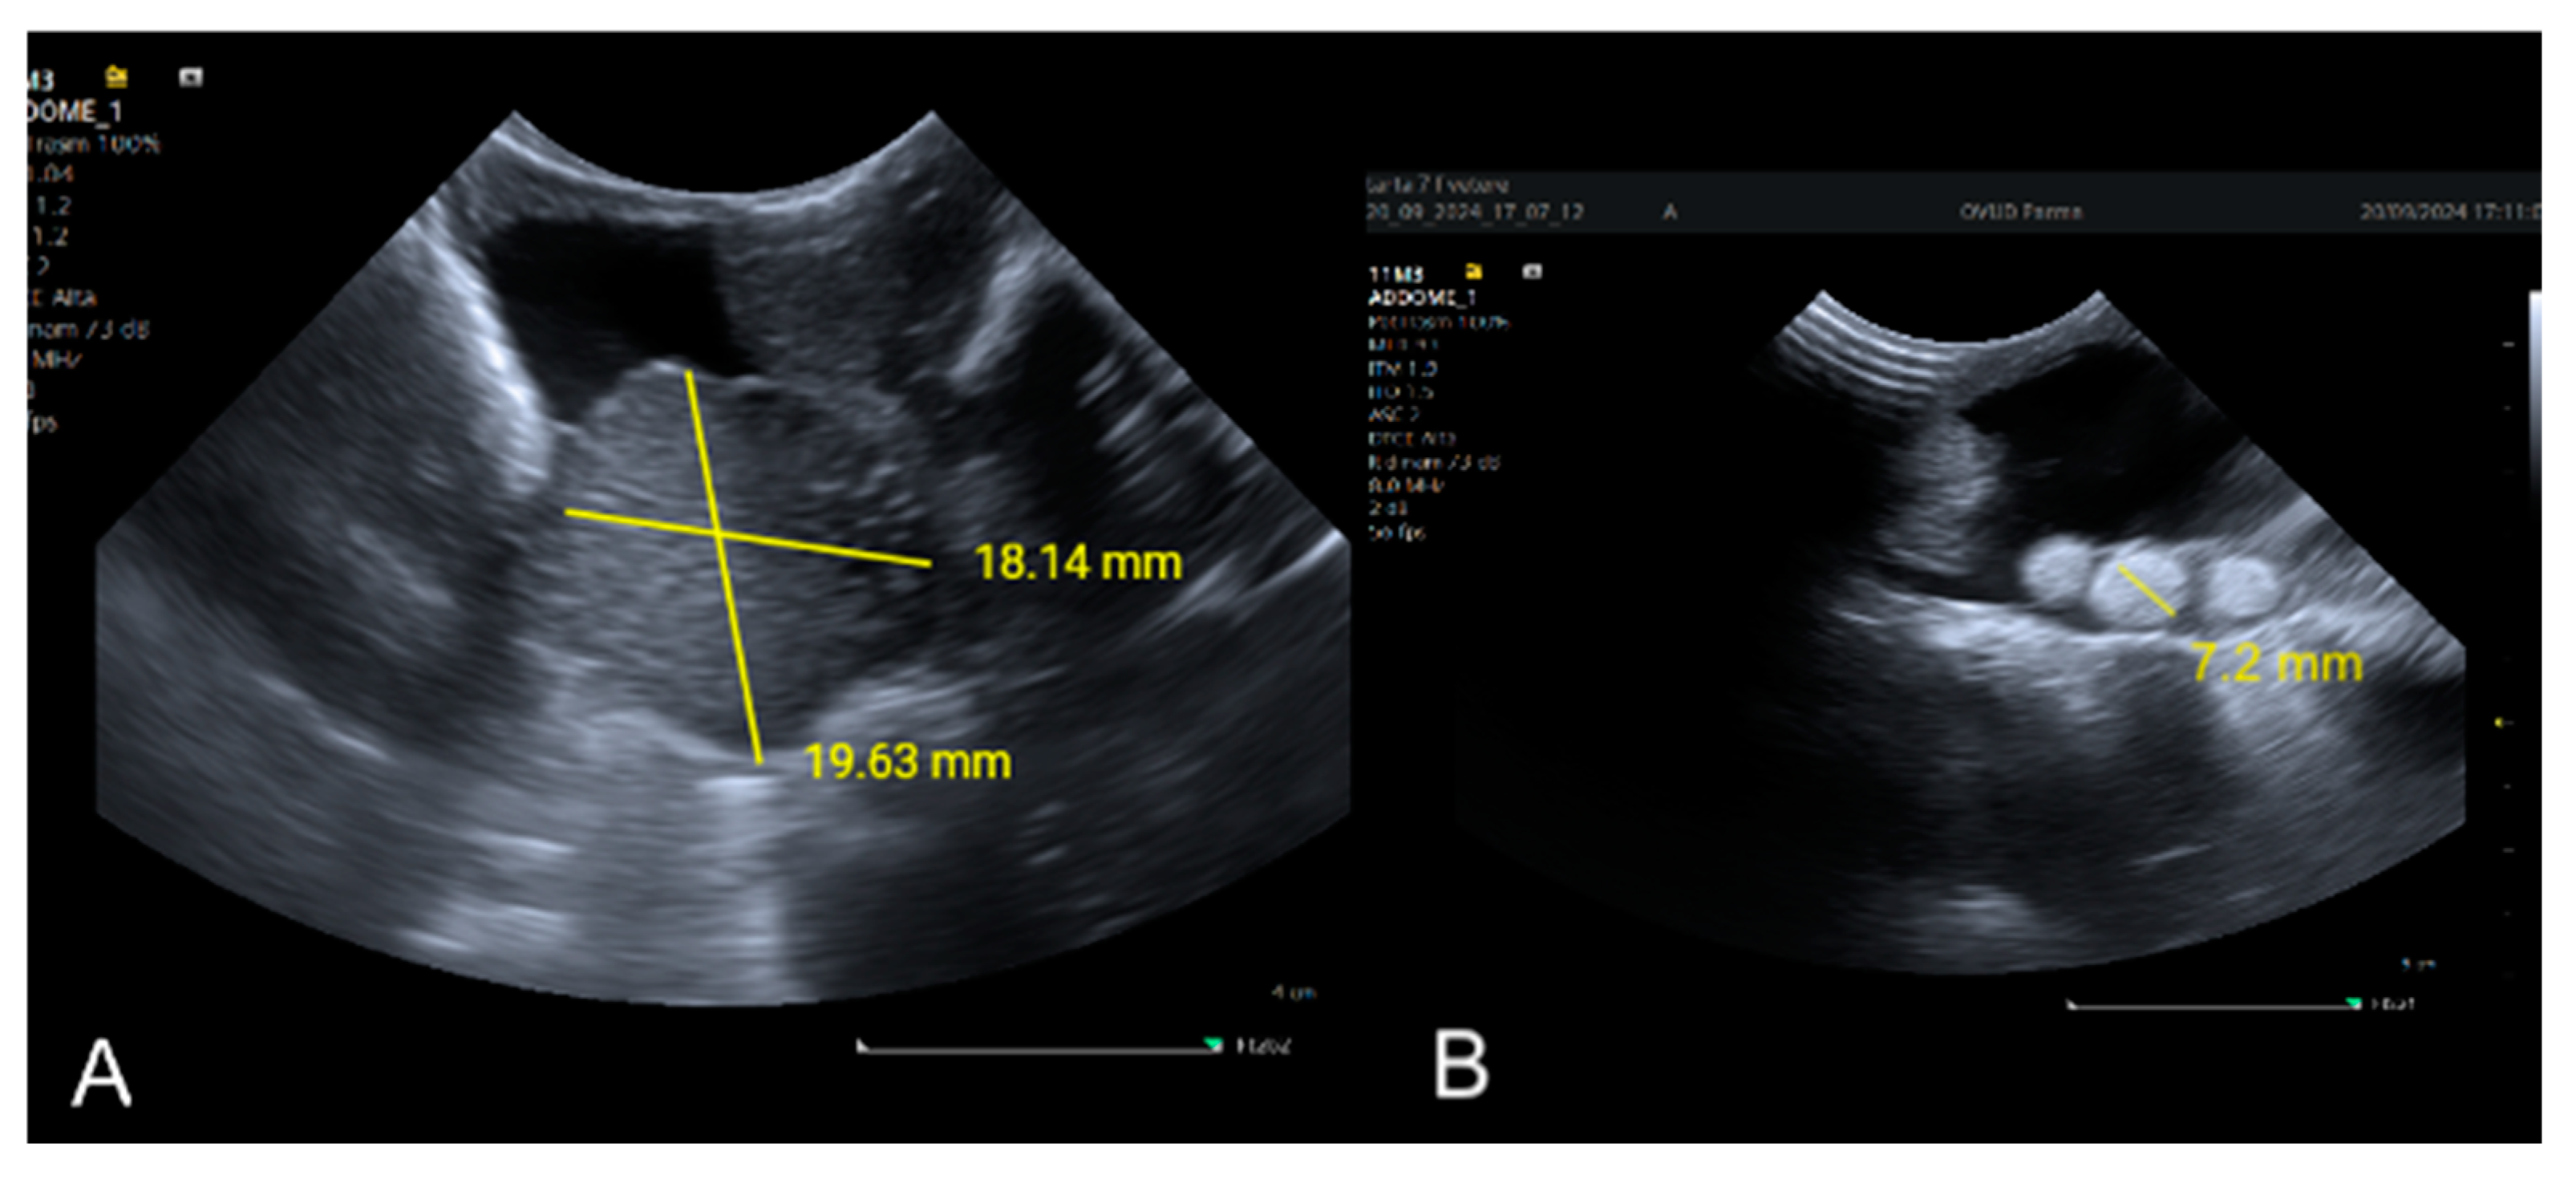

5.4. Ultrasound